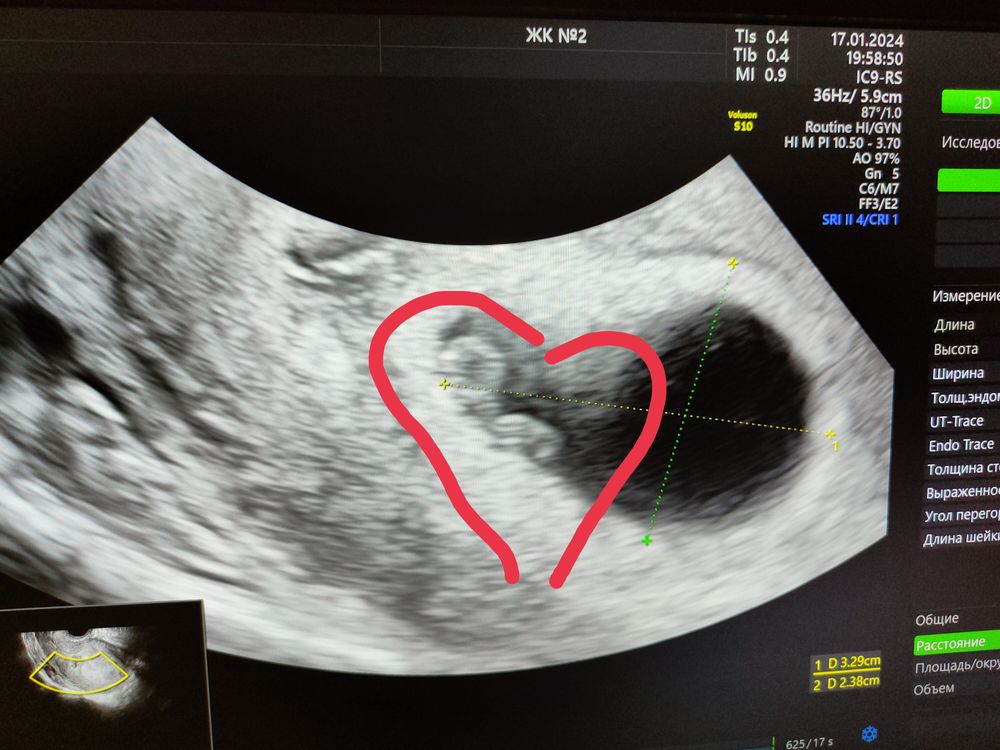

Ну что с отличным меня УЗИ ❤️

Девочки только с УЗИ.все хорошо у нас. ❤️ Забилось 130 ударов! КТР 6 мм..это просто не передать эмоции! Я так боялась не развивающей. Узист сказал главное чтобы грудь наливалась , если пропали все признаки это повод переживать.